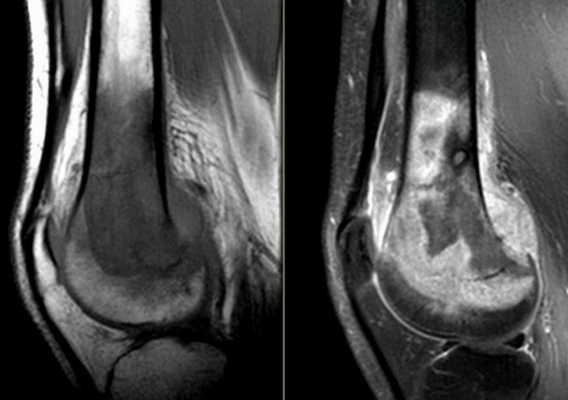

Изменения головки большеберцовой кости на томограмме

Компьютерная томография колена

КТ колена

С помощью компьютерной томографии визуализируют нарушения связочного аппарата, костных суставных поверхностей, гиалинового хряща, синовиальной оболочки и капсулы сочленения. Ограничение подвижности и боль возникают чаще при травмах, воспалительных и дегенеративных патологиях.

КТ коленного сустава позволяет диагностировать хондромаляции (разрушение хряща), повреждения менисков, разрывы крестообразных связок. В результате контрастной процедуры выявляют онкологические процессы, заболевания сосудов, липоартрит и пр.